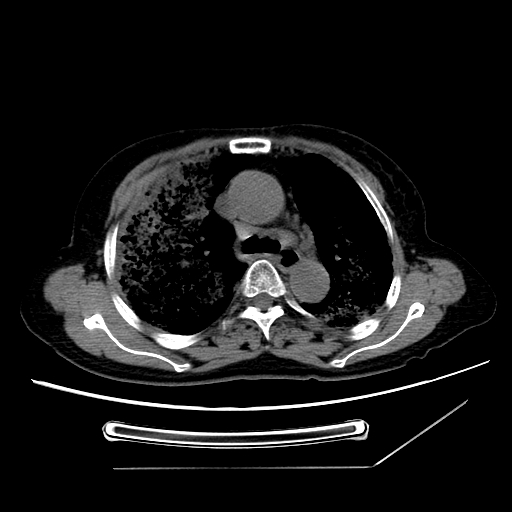

标题: CT25393:病人45岁,咳嗽,吐黄痰带血丝,发热,胸闷月余 [打印本页]

标题: CT25393:病人45岁,咳嗽,吐黄痰带血丝,发热,胸闷月余

1、左肺中央型肺癌并双肺弥漫性转移   2、双肺部感染    3、肺大泡     4、左侧胸腔积液

双侧肺弥漫性病变,可见“空泡征”及“蜂窝征”,考虑肺泡癌可能性大,左侧胸腔积液,考虑胸膜受累可能!

考虑肺泡癌,建议排除感染。

考虑肺泡癌

1)不排除肺泡癌可能。2)左侧胸腔积液。